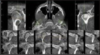

Perfectly

7

Q

CBCT: continous or pulsed

A

pulsed preferred since it reduces patient radiation dose

How well did you know this?

1

Not at all

2

3

4

5

8